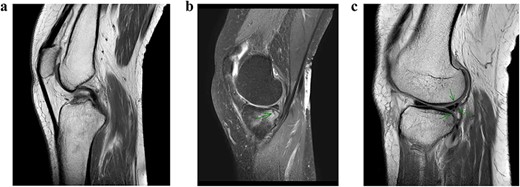

A conventional radiograph of the left knee showed no abnormalities (Fig. 1). An MRI scan was performed that confirmed an ACL tear accompanied by a grade 1 MCL tear, a lateral meniscal tear and a small incomplete fracture of the posteromedial tibia plateau (Fig. 2a–c). Arthroscopy of the knee was scheduled because of catching with persistent limited range of motion despite physical therapy 10 weeks after initial trauma.

MRI scan of the left knee. (a) ACL rupture. (b) Small incomplete fracture of the posteromedial tibia plateau. (c) Partial lateral meniscal tear.